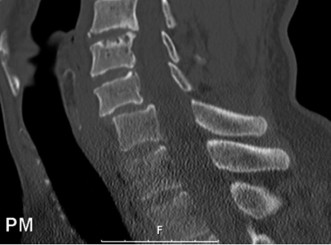

Initial trauma radiographs demonstrated a loss of anterior and middle column height at L1, with a focal kyphotic deformity. However, plain films are vastly insufficient for definitive surgical planning in thoracolumbar trauma. A high-resolution, fine-cut Computed Tomography (CT) scan of the entire spine was obtained. The CT images confirmed an L1 burst fracture with severe comminution of the vertebral body. Sagittal and axial reconstructions revealed 50% canal compromise secondary to a large retropulsed bone fragment originating from the posterosuperior aspect of the L1 vertebral body. Furthermore, the CT demonstrated 25 degrees of segmental kyphosis measured from the superior endplate of T12 to the inferior endplate of L1.

Magnetic Resonance Imaging and the Posterior Ligamentous Complex

To definitively assess the integrity of the soft tissue stabilizers and the neural elements, a Magnetic Resonance Imaging (MRI) scan without contrast was performed. Historically, textbooks propagated the "50-50-25 rule," suggesting that a burst fracture was inherently unstable if it exhibited >50% canal compromise, >50% loss of vertebral body height, or >25 degrees of kyphosis. Modern spine trauma surgery has largely debunked this rigid radiographic dogma. We now understand that these bony metrics alone do not dictate mechanical instability. The true arbiter of stability is the Posterior Ligamentous Complex (PLC).

The MRI, particularly the Short Tau Inversion Recovery (STIR) and T2-weighted sagittal sequences, provided the definitive diagnosis. The images demonstrated profound hyperintensity and discontinuity of the ligamentum flavum, the interspinous ligaments, and the supraspinous ligaments at the T12-L1 level. The facet joint capsules were also disrupted, indicated by fluid within the joints. This complete failure of the PLC means the posterior tension band is gone. Regardless of the bony parameters, this spine cannot resist physiological flexion loads. If treated non-operatively, this injury will inevitably lead to progressive kyphosis, delayed neurological deficit, and intractable pain.